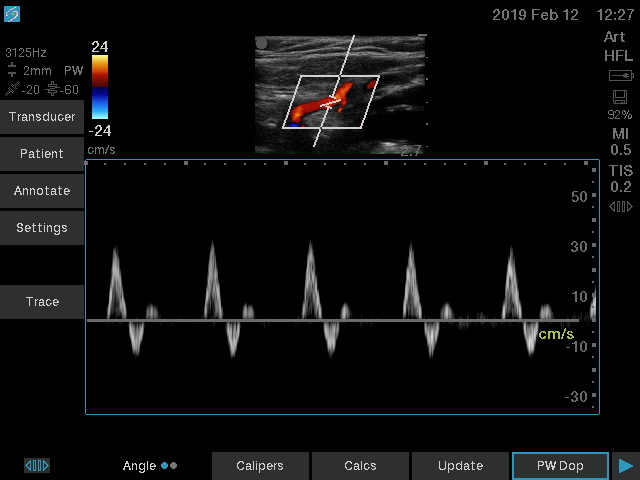

| کاربری | سونوگرافی و اکوکاردیوگرافی |

| کاربری | سونوگرافی و اکوکاردیوگرافی |